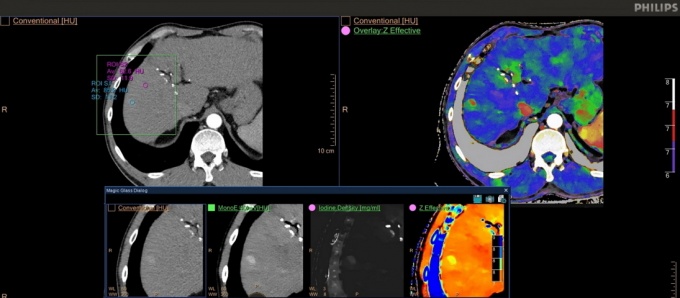

ÀÓ»ó ¼º´ÉÀÌ ÇÑÃþ °­È­µÈ ¾ÆÀÌÄÜ ½ºÆåÆ®·² CT(IQon Spectral CT)µµ °ø°³ÇÑ´Ù.

±âÁ¸ CT¿Í °°Àº ÃÔ¿µ ¹æ¹ýÀ¸·Î ½ºÄµÇØ ÀÏ¹Ý CT ÀÚ·á¿Í ÀÎü ³»ºÎ Á¶Á÷ÀÇ ±¸¼º ¹°Áú Á¤º¸¸¦ ´ãÀº ½ºÆåÆ®·² µ¥ÀÌÅ͸¦ µ¿½Ã¿¡ ¾òÀ» ¼ö ÀÖ´Ù.

»çÀü¿¡ °èȹÇÏÁö ¾Ê¾Æµµ CT ÃÔ¿µ ÈÄ Çʿ信 µû¶ó µ¥ÀÌÅ͸¦ ºÒ·¯¿Í ½ºÆåÆ®·² ¿µ»ó Á¤º¸¸¦ ºÐ¼®ÇÒ ¼ö Àִ٠ƯÈ÷ ÇÏ·ç ÃÖ´ë 200¸íÀÇ ½ºÆåÆ®·² µ¥ÀÌÅ͸¦ À籸¼ºÇÒ ¼ö ÀÖ¾î ±âÁ¸º¸´Ù ´õ¿í dzºÎÇÑ Áø´Ü Á¤º¸¸¦ ¾ò°Ô µÆ´Ù.